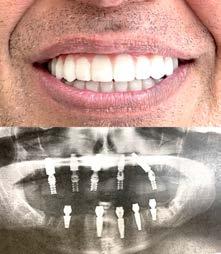

Одна из недавних операций:

Все-на-5-ти имплантах + несъемные зубы за 1 день

Высококлассные услуги по Зубной Имплантации в современной клинике, лимиторованной на установку имплантов.

* - установка 1 (одного) импланта не включая абатмент и коронку. Имплантация будет производится одним из специалистов клиники под руководством доктора Александра Антипова, челюстно-лицевого хирурга.

# 4 (2023) • 26 февраля Газета «Диаспора» – все о нас с вами ПО ВОПРОСАМ РАЗМЕЩЕНИЯ РЕКЛАМЫ ОБРАЩАЙТЕСЬ ПО ТЕЛЕФОНУ: (916) 487-9701 или (916) 705-0739 10 Замещение всех зубов на 4-х, 6-ти имплантах Одиночные импланты Несколько имплантов ИМПЛАНТАЦИЯ ЗУБОВ Установка одного импланта от FREE Consultation and CT-Scan